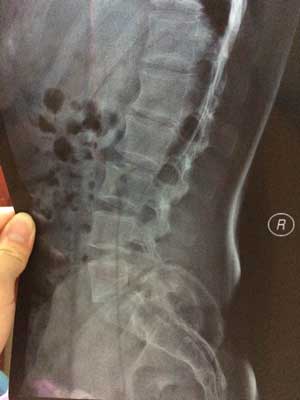

(图:于先生检查时的x光片,主治医生诊断为强直早中期)

CT检查:腰椎正侧位片及双侧骶髂关节正位片示,腰椎无异常,双侧骶髂关节间隙无变化,骶髂关节骨质密度增高,边缘模糊,局部有虫蚀样改变。最终确定患上强直性脊柱炎,已发展至早中期。